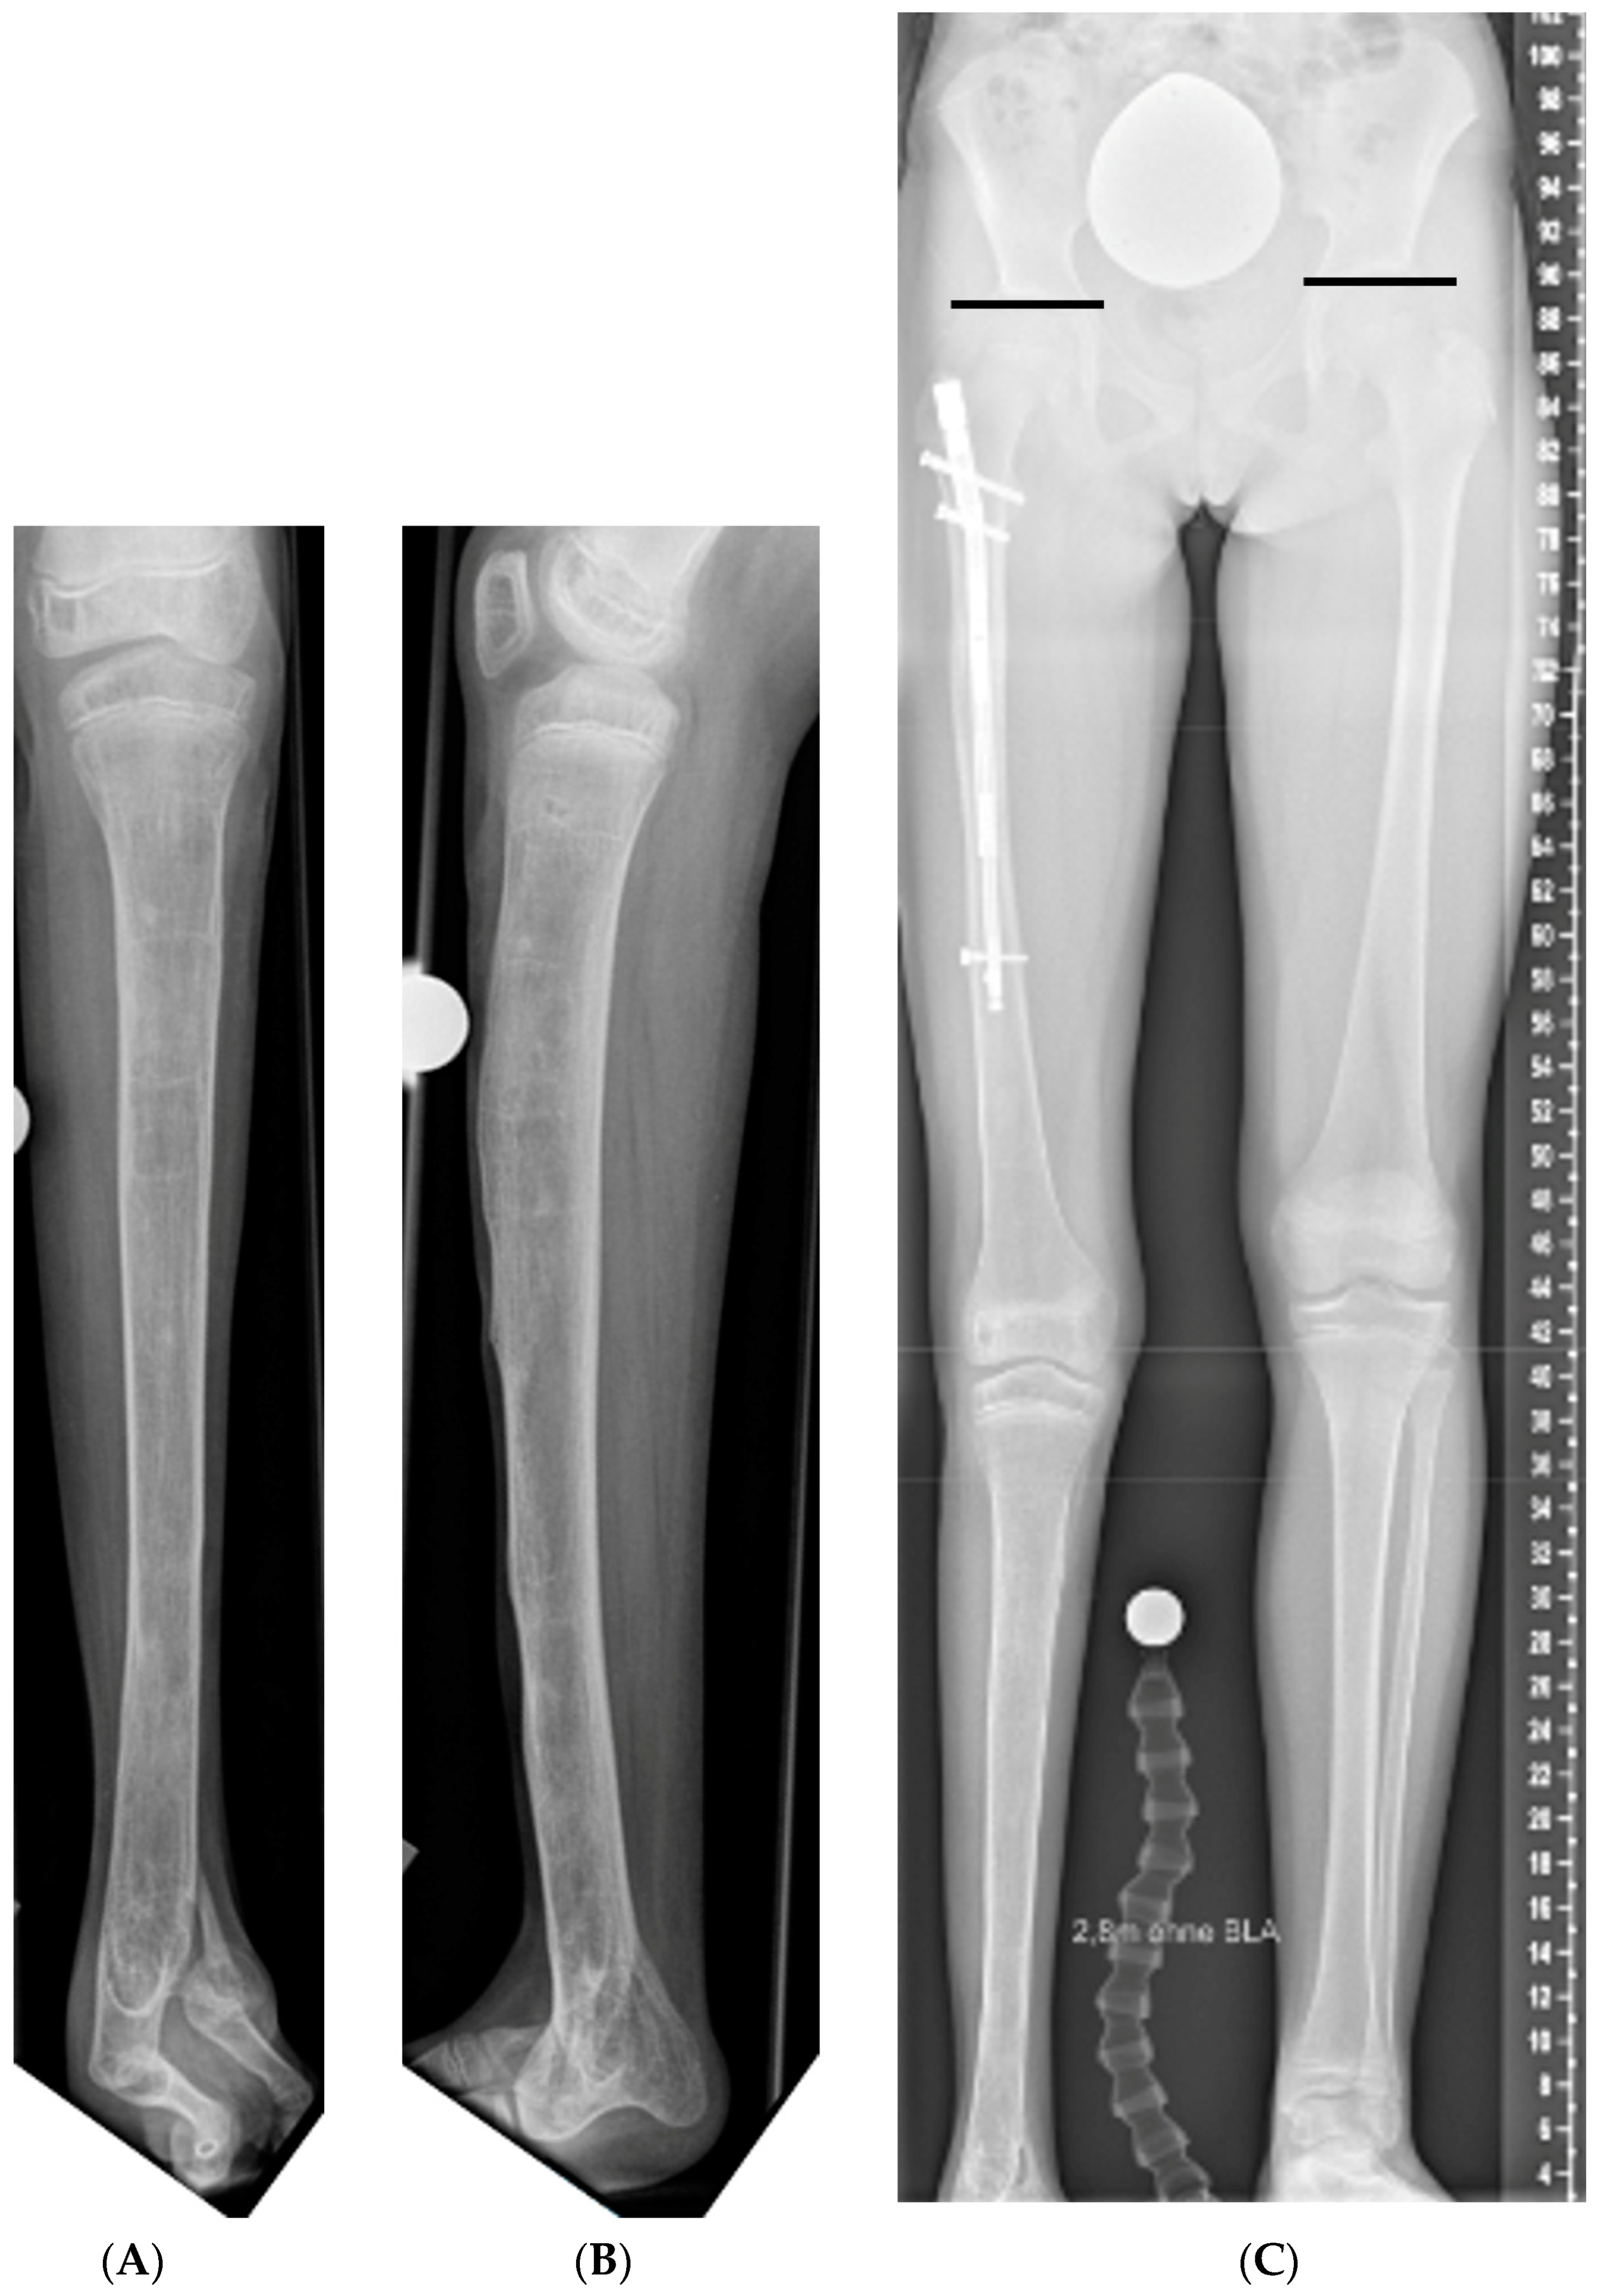

3.4. Leg Length Equalization

3.5. Axis Realignment